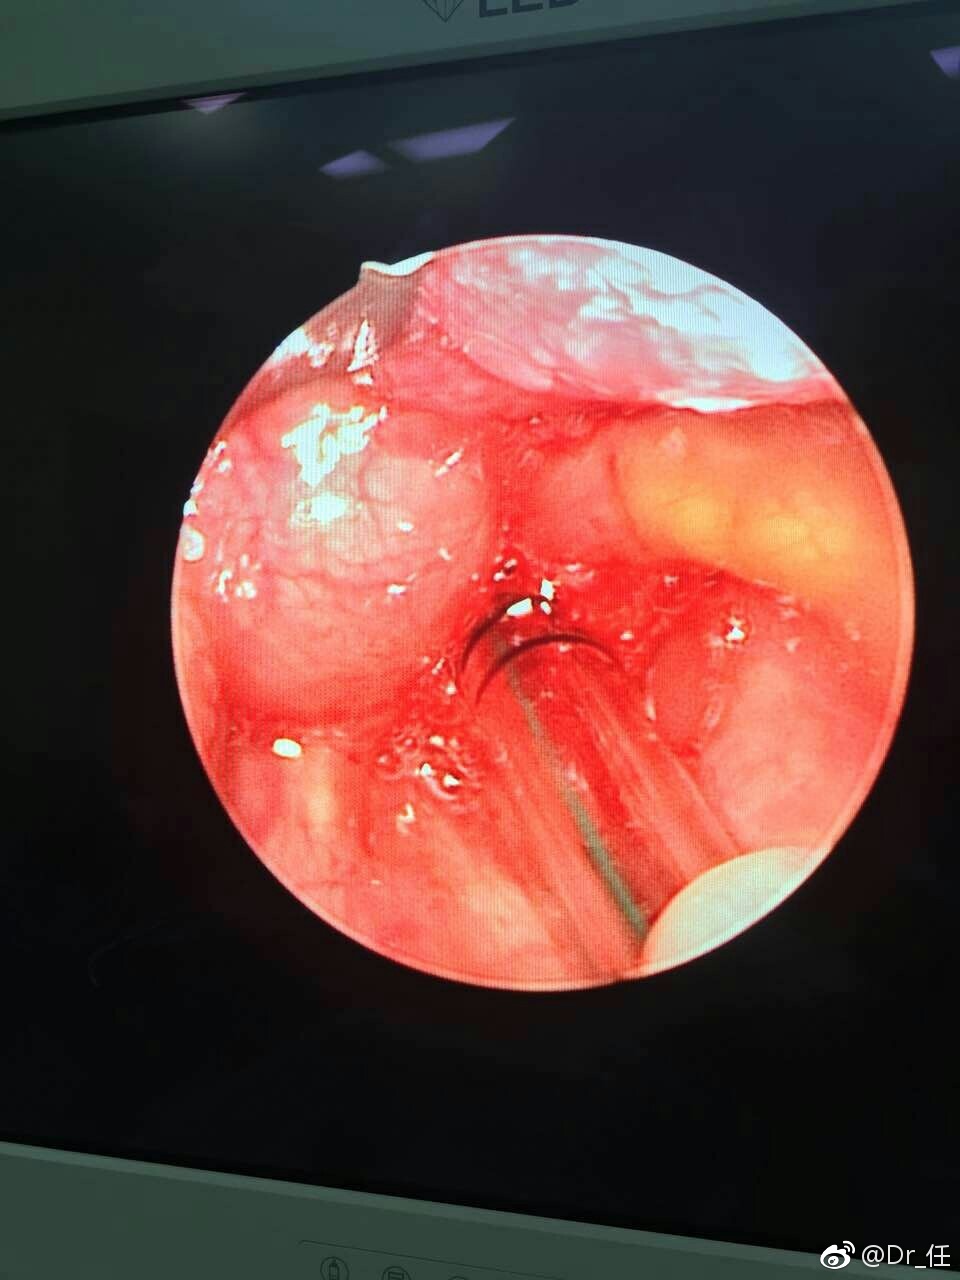

新生儿喉喘鸣也可能是会厌囊肿惹的祸|新生儿

会厌囊肿手术其实很简单,治疗的方法要根据会厌囊肿的部位和大小来决定。对于较小的囊肿,在门诊喉镜下用

健康咨询描述:会厌囊肿手术:该手术你好,会厌囊肿容易堵塞气管造成憋气,呼吸困难,受体位影响比较大。会